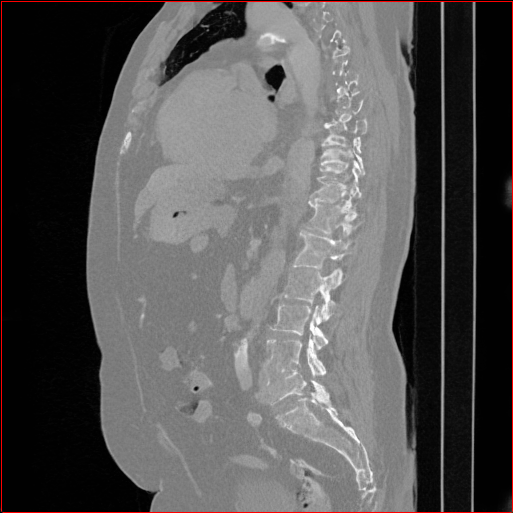

Figure 2: Qualitative comparison across axial (top row), sagittal (middle row), and coronal (bottom row) views. Columns correspond to different methods. MAISI-DDPM and MAISI-v2 in this figure are unconditional synthesis which do not use ControlNet or segmentation maps.

Qualitative Evaluation:

Figure 2 presents representative slices from the axial, sagittal, and coronal planes. GenerateCT (Hamamci et al. 2024) is a 2D model, so it lacks inter-slice consistency, leading to poor image quality in the sagittal and coronal views. MedSyn (Xu et al. 2024) produces noticeably blurry results with mosaic-like artifacts, such as region inside the red box. HA-GAN (Sun et al. 2022) generates visually sharp images but with mosaic-like artifacts, such as region inside the red box. Also, its voxel spacing is not available, which limits its applicability in real-world medical imaging tasks. Moreover, all three methods are restricted to synthesizing small anatomical regions. In contrast, both MAISI and MAISI-v2 are capable of generating high-quality 3D volumes that span larger body regions while preserving fine anatomical details and realistic structure.